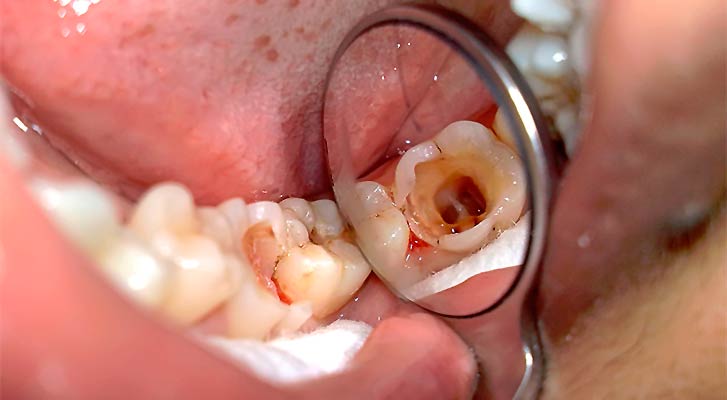

Фото и рентген

2. Визуальный осмотр: Врач проводит тщательный осмотр полости рта, обращая внимание на состояние зубов, десен и окружающих тканей. Он ищет признаки кариеса, трещин или других повреждений, которые могут указывать на воспалительный процесс в пульпе.

5. Рентгенография: Рентгеновские снимки являются важным инструментом в диагностике пульпита. Они помогают выявить наличие кариеса, воспалительных процессов в околозубных тканях, а также оценить состояние корней зуба. На рентгенограммах могут быть видны изменения, указывающие на наличие инфекции или абсцесса.